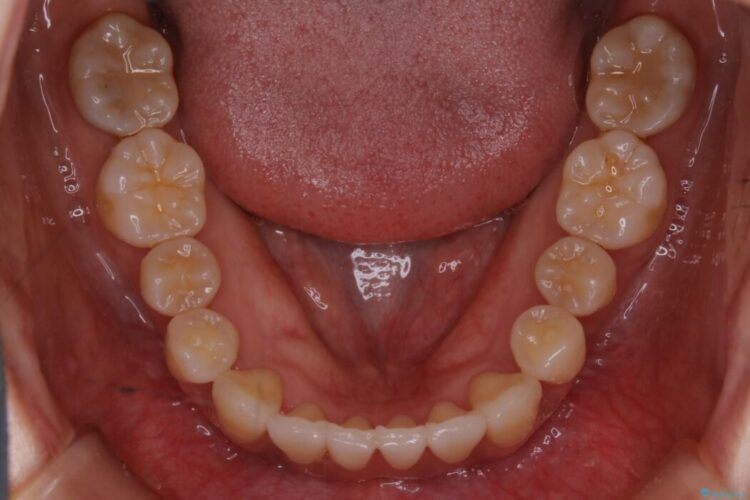

前歯のガタガタを気にされて来院されました。

検査の結果、骨の厚みに余裕がないことが判明しましたので、幅の拡大と歯の側面を削るIPRでは歯周病に対する不安を拭いきれないと判断しました。

よってマイクロインプラントを用い、奥歯から順番に遠心移動させることによってスペースを確保することにしました。